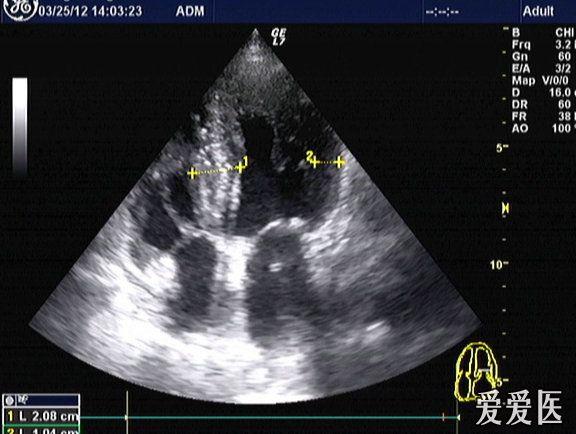

肥厚型心肌病超声图片,肥厚型心肌病心电图

第2节 肥厚型心肌病

肥厚型心肌病?梗阻还是非梗阻?

肥厚型心肌病sam征图片